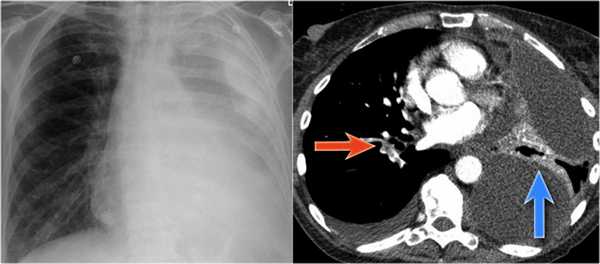

Обратите внимание на правую междолевую артерию (красная стрелка) и границы правых отделов сердца (синяя стрелка).

- Минимальное уменьшение объема легкого без подъема левого купола диафрагма.

- В загрудинном пространстве визуализируются изменения высокой плотности, которые спавшейся верхней доли левого легкого.

- Корень левого легкого патологичен, что может соответствовать образованию, обтурирующее просвет бронха.

- Выше перечисленные находки наводят на мысль, что это ателектаз верхней доли левого легкого.

На КТ снимках синей стрелкой указан долевой ателектаз, а красной стрелкой опухоль, которая обтурирует левый верхний долевой бронх (центральный рак легкого.

Ателектаз верхней доли левого легкого с типичным симптомом воздушного серпа (Luftsichel sign — luft(air)+sichel(sickle)), обусловленный гипервентиляцией верхнего сегмента нижней доли левого легкого на фоне коллапса верхний доли левого легкого. Гипервентилируемый

сегмент визуализируется на прямой рентгенограмме от дуги аорты до апикальной части легкого.